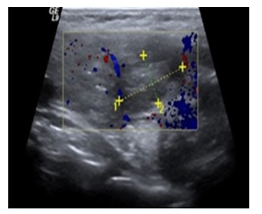

The patient underwent radical node dissection (45 lymph nodes), who’s biopsy revealed reactive histiocytosis. FNB of the thyroid lesion (Figure 2) depicted metastatic infiltration from the same ovarian carcinoma. After this diagnosis, a right lobe lobectomy was performed. FNA of the liver, under ultrasound guidance, indicated fatty liver and fibrosis with no signs of malignancy. Thyroid biopsy confirmed the diagnosis of malignant metastatic lesion 2x1, 5cm by the ovarian carcinoma (Figure 3,4). The 7 local lymph nodes were negative for infiltration from the neoplasm. The patient started chemotherapy with CDDP/Docetaxel with adjuvant intends, after 4 weeks, mainly to treat the potential mediastinal metastatic lymphadenopathy (we have no biopsy from this site at present).

Figure 3 Thyroid infiltration by high grade serous carcinoma with classic cytological figures. (H & E X 200).